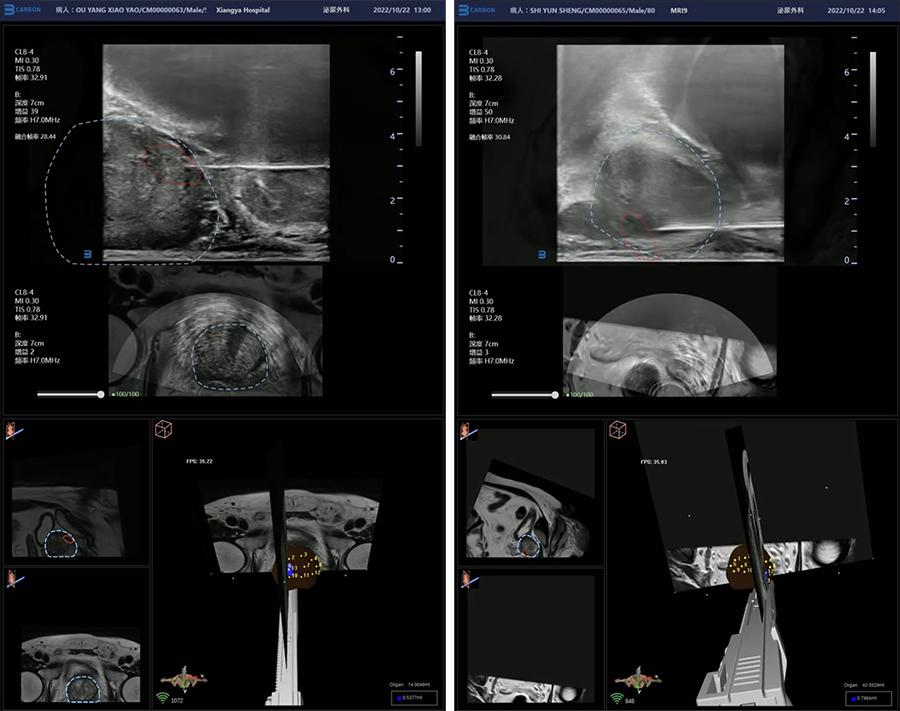

在近期的MRI—TRUS经会阴穿刺活检手术中,为了更快的配准,减轻患者的痛苦,术前王睿哲和刘培华两位博士应用3D重建、自动配准技术,在2分钟快速完成了患者MRI数据与超声实时数据的多模态影像配准,大大缩短了术前准备,减轻了患者的痛苦。

为了更精准的定位病灶,术中通过AI人工智能自动分割器官确定前列腺轮廓,再基于T2WI/DWI/ADC多模态图像,快速精准定位了病灶,实现了前列腺癌靶目标的跟踪与标注,确定了前列腺靶向穿刺点。

在经会阴穿刺过程中,通过电磁导航实时显示穿刺针等手术器械的运动轨迹,实现了对穿刺路径的可视化、精准引导;再通过双平面腔内探头、AI针尖识别,确定靶向穿刺的高度和深度,提高了靶向穿刺的精准度。与此同时,VENUS的活检组织取样安全区域标识功能,帮助刘培华教授有效避免了穿刺误差,防止误伤,为患者带来了更精准的诊疗。